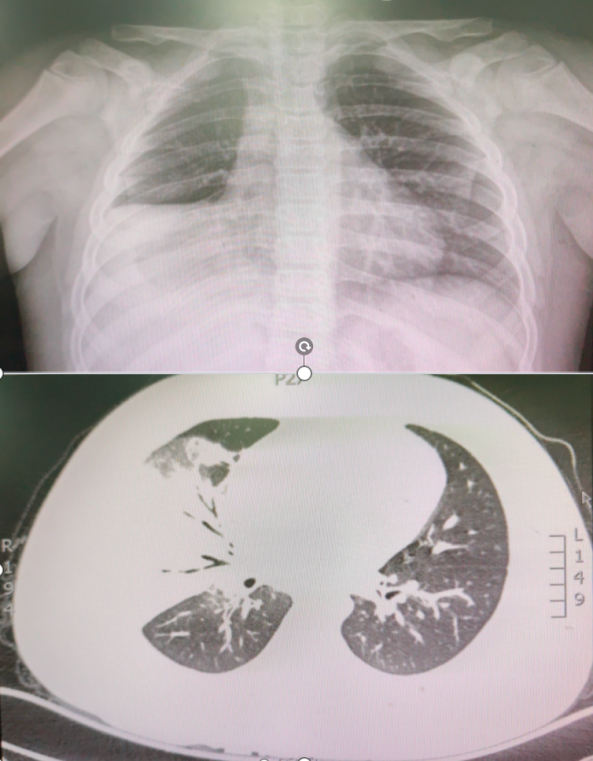

三、胸部影像学(胸片/胸部CT):CT诊断意义高于胸片(医生会根据病情和病程来建议检查)